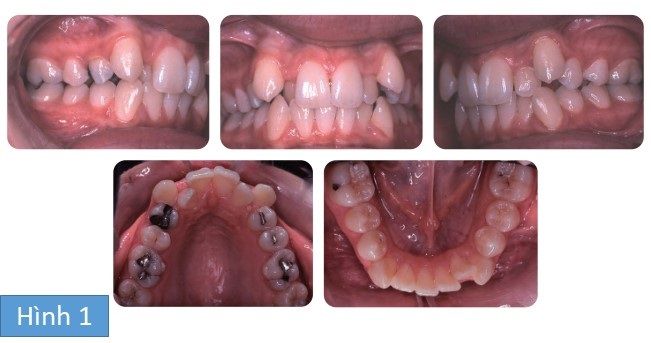

Bệnh nhân nữ 13 tuổi tới phòng khám với than phiền răng chen chúc và không hài lòng với hình dáng răng nanh của mình. Không có tiền sử bệnh lý liên quan. Cô bé có sai khớp cắn hạng I trên nền xương hạng I và kích thước dọc trung bình, phức tạp bởi chen chúc và lệch đường giữa răng.